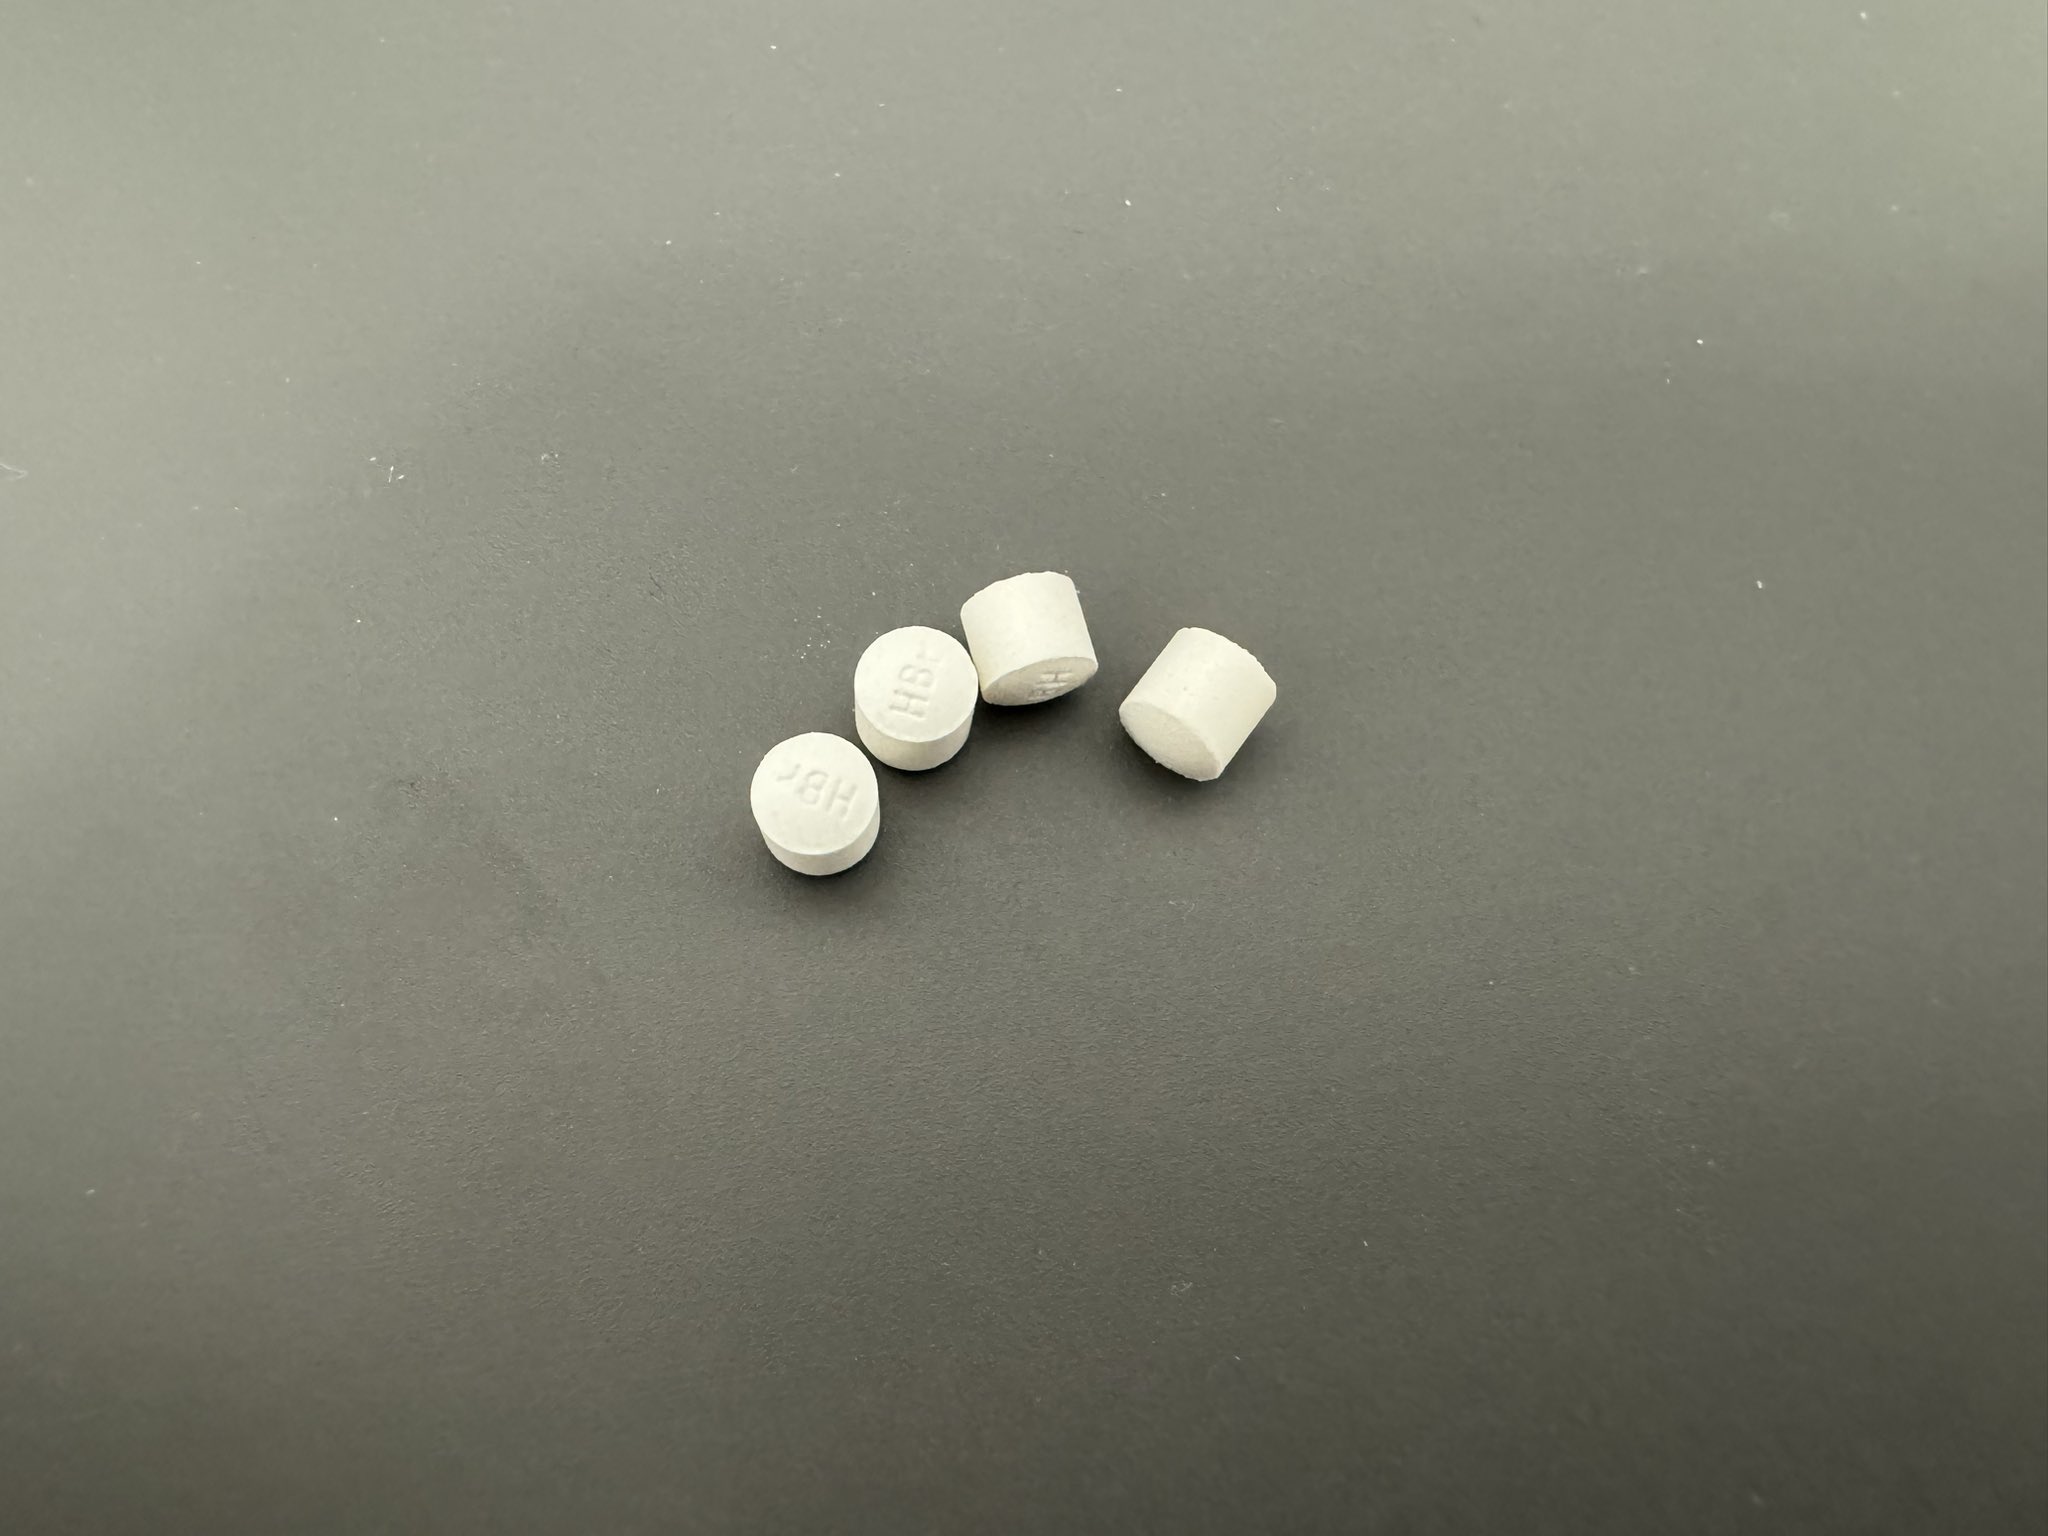

金刚烷胺会对神经系统造成长期/不可逆的影响

首先多巴胺系统

金刚烷胺作为多巴胺释放促进剂,在长期使用或过量下可能导致:

-DA系统适应性衰竭(Receptor downregulation)

-药源性多巴胺枯竭综合征:表现为认知退化、动机缺失(apathy)、情绪迟钝等。

NMDA

虽然金刚烷胺是弱NMDA拮抗剂,但长期使用可能导致:

-突触可塑性损伤(LTP/LTD受阻)

-情景记忆下降、学习能力减退

-焦虑、攻击行为升高

-神经元代谢负荷增加,增加兴奋毒性风险

金刚烷胺提高兴奋性毒性(NMDA活性失衡、多巴胺代谢紊乱),与致幻剂合用或交替用药会:

-加剧皮层-边缘系统的不稳定性(例如海马体、前额叶)

-增加精神病风险(psychosis risk)

-导致长期认知损伤与感知畸变的残留症状(HPPD-like states)

另外有导致神经适应性结构改变

动物研究提示,金刚烷胺长期使用可能导致:

-树突棘数量下降

-突触可塑性衰退

-神经炎症因子(如IL-6)升高,为不可逆脑损伤打下基础

2025-04-29 11:45:39 UTC

简版

金刚烷胺不但无法提供真正的致幻体验,反而会破坏大脑、干扰神经系统,带来无法逆转的损害。

短期风险:

-幻觉质量差、碎片化,常伴恐惧、迷惑、妄想

-谵妄状态(严重的意识混乱)

-焦虑、失眠、暴躁、攻击性升高

-心跳紊乱、口干、头晕、甚至癫痫发作

长期风险:

-损伤大脑中的多巴胺与谷氨酸系统

-学习能力下降、情绪变平淡、认知迟钝

-增加患上药源性精神障碍的风险

炽烈已极 @AnIncandescence金刚烷胺会对神经系统造成长期/不可逆的影响